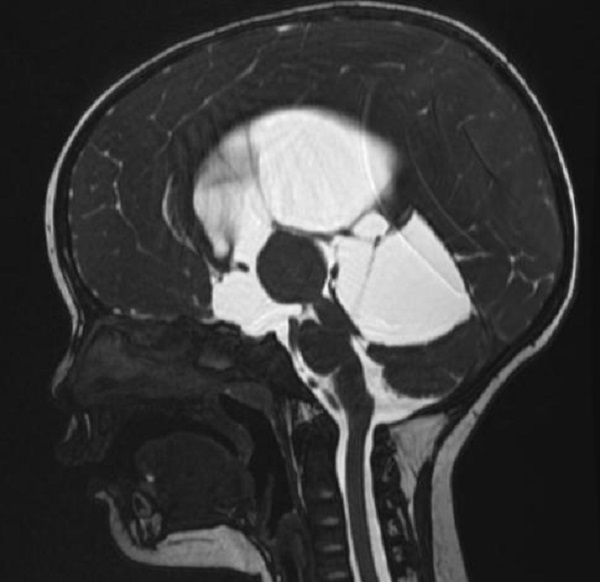

一歲多的赫赫小朋友自出生頭顱就比同齡小孩大,近半月來進食后出現(xiàn)嘔吐,伴頭痛,在當?shù)蒯t(yī)院及省內(nèi)多家醫(yī)院治療不見好轉(zhuǎn),于是來到二一五醫(yī)院神經(jīng)重癥監(jiān)護室,因患兒近半月多不能正常進食,入院時精神萎靡,頭顱MRI檢查提示“腦室系統(tǒng)擴大,雙側(cè)腦室額角周圍間質(zhì)水腫,左側(cè)丘腦占位病變,鞍上池及小腦上池擴大”。

為進一步鑒別腦積水類型,行磁共振3D FIESTA序列檢查可見側(cè)腦室擴大明顯,中腦導水管中段阻塞、三腦室底受壓下陷,診斷梗阻性腦積水。